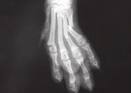

Fractura diafisaria de los metacarpianos

Fractura diafisaria de los metacarpianos. Son lesiones relativamente frecuentes, y algunos autores citan el hecho de que se presente muchas veces la fractura de varios metacarpianos. Las fracturas de los metacarpianos 1ro. Y 5to. En ocasiones producen cierta incapacidad de la mano cuando no ha sido efectivo el tratamiento; no ocurre así con los tres metacarpianos centrales que forman el componente fijo del metacuerpo, en los cuales la consolidación con algunos pequeños desplazamientos no compromete la lesión.